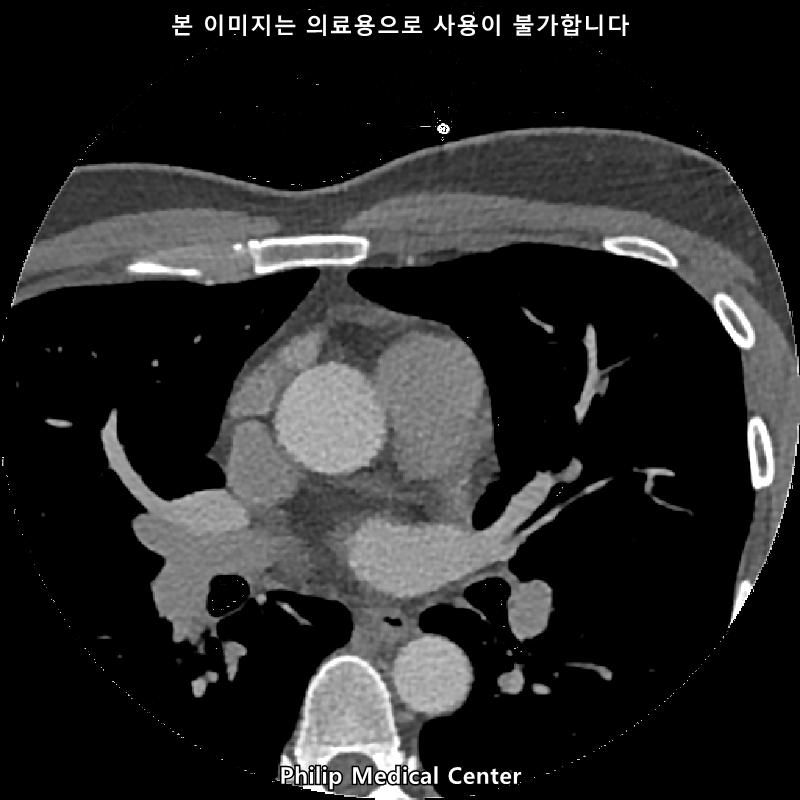

안녕하세요, 저선량 폐CT 검사결과 아래와 같이 나왔는데요, 어떤의미일까요ㅠㅜ

(우측 폐첨부에 경미한 섬유성변화와 우중엽에 약 3mm크기의 결절)

• 2번 째 사진

우측 폐첨부에 경미한 섬유성변화와 우중엽에 약 3mm크기의 결절이라는 것은 이상 소견이긴 하지만 보통 경과관찰을 하는 소견입니다.